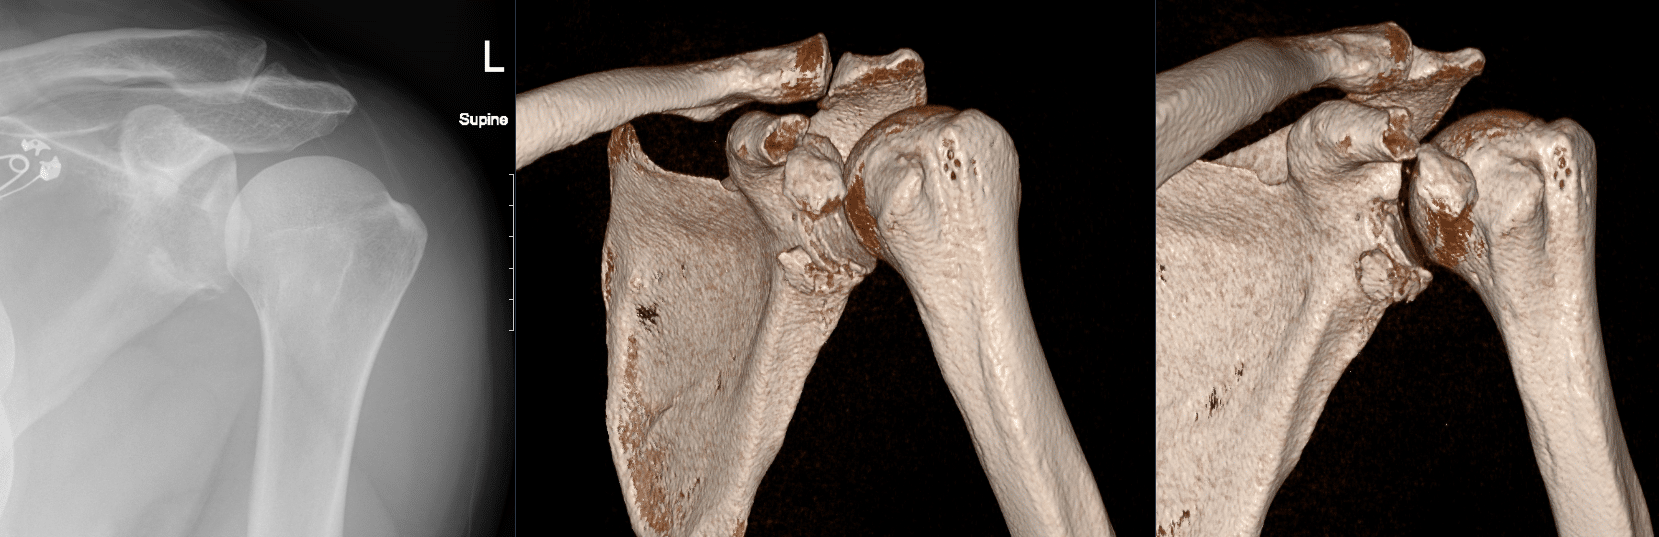

CT Case 104

A 45 year old female presents with shoulder pain following a seizure.

She is found to have a swollen painful left shoulder with reduced range of motion in all directions. Her left arm is neurovascularly intact.

An X-ray of the shoulder found an enlocated shoulder with an irregularity around the glenoid rim.

A CT of the left shoulder is arranged.

Describe and interpret the CT scan

1. Hill-Sachs deformity in the posterior aspect of the humerus.

2. Comminuted displaced osseous (bony) Bankart lesion involving the anterio-inferior glenoid fossa (6-10 o’clock).

3. Comminuted laterally displaced fracture of the coracoid process.

4. Associated joint effusion and surrounding soft tissue haematoma.